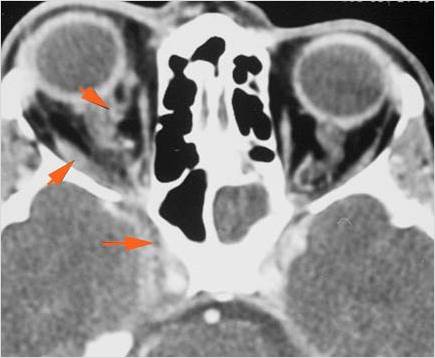

Orbits

The extraconal orbital fat is abnormal.

There is a subperiosteal abscess or edema along the medial wall, roof or floor of the orbit.

The extraocular muscles are swollen or otherwise abnormal.

There is bone erosion along the walls of the orbit.